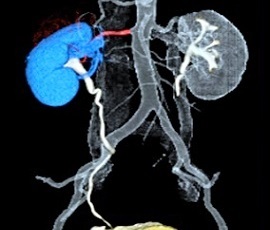

腎ダイナミックCT(3D)画像